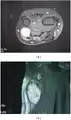

• Pleural schwannoma is extremely rare. A unique subtype of schwannoma that typically develops in superficial (cutaneous or subcutaneous) sites and may be identified by its development pattern, which is plexiform (intraneuralnodular)[7][8].The correlation with schwannoma predisposition disorders like NF2 and schwannomatosis, however, is minimal (approximately 5 percent of cases)[9].These tumors might lack a capsule or be less encapsulated than a typical schwannoma.More challenging to identify from MPNST are the infrequent plexiform schwannomas that develop in deep anatomical sites, such as soft tissue[10] or major peripheral nerves.[11] These tumors may exhibit enhanced cellularity and mitotic activity. Although the likelihood of these tumors developing into cancer is extremely low, local recurrence is possible in around half of cases. On MRI, it usually shows hyper or iso-intensity on T1-weighted images and heterogenous hyperintensities on T2 weighted images. Pleural schwannoma typically shows fatty degeneration, hemorrhage, perivascular hyalinization, and cystic formation thus giving heterogenous hyperintensities on T2 weighted images. Complete surgical removal of pleural schwannoma is the usual treatment.[12]